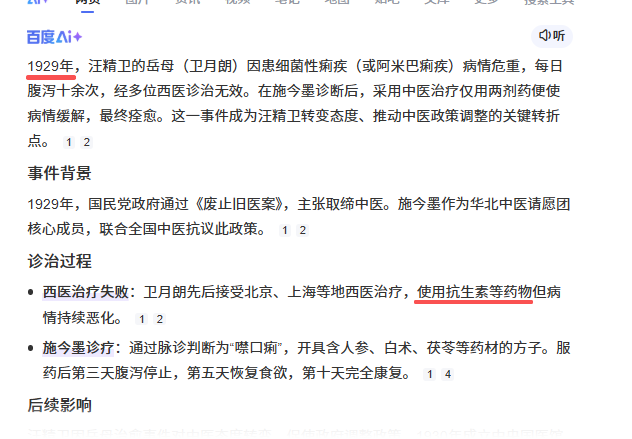

带来了诚实与责任心、职业道德两个高贵品德。 医术很多知友都说了。我不再赘述,我强调的讲一下品德,人的珍贵的品德。 也就是诚实,不撒谎。以及勇敢的责任心、职业道德。 1、职业道德。 希波克拉底誓言中文译文: 作为一名医疗工作者,我正式宣誓: 把我的一生奉献给人类; 我将首先考虑病人的健康和幸福; 我将尊重病人的自主权和尊严; 我要保持对人类生命的最大尊重; 我不会考虑病人的年龄、疾病或残疾、信条、民族起源、性别、国籍、政治信仰、种族、性取向、社会地位或任何其他因素; 我将保守病人的秘密,即使病人已经死亡; 我将用良知和尊严,按照良好的医疗规范来践行我的职业; 我将继承医学职业的荣誉和崇高的传统; 我将给予我的老师、同事和学生应有的尊重和感激之情; 我将分享我的医学知识,造福患者和推动医疗进步; 我将重视自己的健康,生活和能力,以提供最高水准的医疗; 我不会用我的医学知识去违反人权和公民自由,即使受到威胁; 我庄严地、自主地、光荣地做出这些承诺。 1895年中日甲午战争,在中国的西医与西医护士自然而庄严、郑重的履行了自己的誓言。 1895年为了应对中日甲午战争,李鸿章高薪招聘了大批的中医当做军医,然后,日本大炮一响,中医大师们纷纷撂下手中的伤员就跑,边跑边大喊:咱们快跑啊,咱们不是兵,快点跑啊! 从山海关到威海卫,莫不如此。从重庆到延安,从海河到天津站,概无例外。 最后是中国的西医、西医护士,挺身而出,英勇的在一线救治中国伤兵。 最终李鸿章在天津开了中国第一家西医军医院。 华北的中医大师傅们听了勃然大怒,这事是要来跟我抢饭碗了!于是四处买广告登报纸,用了他们最拿手最擅长的绑架泼污大法,绑架祖宗,绑架中国,说李鸿章用西医是背叛祖宗,是中国的叛徒。最后李鸿章无奈,说那你们来军医院吧,你们来帮助救治。于是施今墨陆仲安们扯高气昂的来到军医院,结果到了一看,到处是缺胳膊断腿拖着肠子满地爬的伤兵,顿时中医大师傅们集体尿了,扭头就跑。此后,中医彻底退出军医界,再也不碰瓷军医。 像我这种看过很多二战苏德回忆录的,也依稀能记得里面一些关于军医的篇章。例如斯大林格勒战役,酷寒之下的行军,德国军医会随时嘴里含一只咖啡,用体温保持吗啡能第一时间可用。代价当然是一路沉默,只能点点头。这种沉默,是人间最珍贵最深沉的沉默,代表了一个职业最崇高无上的道德。 2、诚实。 而西医的诚实,是中医骗最爱的热爱的狂爱的大爱的攻击目标。坟头蹦迪狂欢处。 中医粉最爱举的那些例子,例如陆仲安对胡适的“一剂汤药可治愈糖尿病、肾衰竭”汤,中医粉最爱的,就是胡适糖尿病/肾衰竭,被协和西医宣布不治,然后陆仲安一个中药汤子给治好了。随后就是大肆宣扬。 而你有没有想过,首先就是为什么西医居然会说不能治。你要是我来当西医,虽然1920年还没有胰岛素,但是我手里已经有阿司匹林、磺胺、可乐等一大票的西药。你就是糖尿病,我随便挑几个组合给你用呗,没效果再换,换到你手中没钱了随便找个借口给你打发,让你去找经年成对原配的蛐蛐去,我有一万个办法搪塞糊弄你,而我就不会说我治不了。 而协和的西医,居然告诉胡适,我们没办法治疗。 今天我们反看,不得不说,西医是诚实的。因为1921年胰岛素才发明,而到协和还更需要几年。所以1920年,协和就是没有办法治疗糖尿病。 而胡适实际是肾炎,1920年的协和一样的没有办法治疗。因为青霉素1929年才发明,1943年美国才实现量产。 而肾炎实际是自限性疾病,一般的1-3个月左右也就自己好了。 诚实,是人类的一切的人格品德的最基础的那个,最起码的那个,最低级的要求,是做人的最低级的要求。 而汪精卫岳母痢疾案,更是中医骗张嘴谎的蹦迪处。 |

1929年10月汪精卫才从法国回香港,中医骗那是张嘴就谎啊,还张嘴就汪精卫掌实权,汪精卫1929年10月回来是支持第二次蒋桂战争干老蒋的,他还掌实权。 中医骗的特点就是张嘴就喷谎。主打一个我虽然小学3年级文化,但是够我骗文盲。 1929年,弗莱明刚刚发明抗生素,还只是实验室与论文,这就跑中国来了? 1929年,面对细菌性痢疾,西医就是没有办法治疗,所以就说治不了。1929年弗莱明虽然已经发明青霉素,但是产量感人,当时第一次使用对一个受伤感染的警察,非常有效,但是手中的一点青霉素用完了,于是警察还是shi了。 所以,西医诚实的说,没有办法治疗。 而诚实,是一种多么宝贵的品质。 因为你诚实,你说出来:我不能治疗,那么,这个疾病,就有了解决了一半。 因为你以后,所有的西医,西药,医疗器械从业者,都会想尽办法去攻克这个疾病。 而多少的绝症,曾经的绝症,因为西医的诚实,而最终研究出了真正治疗办法。 例如1921年的胰岛素。 例如1929年的青霉素。 例如1998年的伟哥。 例如2006年的HPV疫苗。 你没有。 3、西医不仅是个自然科学,他还是个管理秩序。 没有人敢保证每个西医从业者都会履行自己的诺言,所以西医除了希波克拉底誓言,还双管齐下,有一套完整的制度。 1)、一人为私,二人为公。西医的任何重大治疗与决策都是多人完成。 手术有术前评估,有术前讨论。 化验师管理体系是单独的。检查技师管理体系是单独的。甚至护士也是单独独立的。护士只是执行医生的医嘱,只是工作关系,不是上下级。护士的管理也是独立的,不归医生管理。麻醉师的管理也是独立的。 而这么多的独立,就是垂直管理,在根子上就切断医生自己一手遮天的可能。 2)、完善的文档记录。 住院病例保存30年。 住院病例需要上级医生签名。需要三级签名。修改需要红笔。 交病案后就归病案室,医生是要不回来了的。因为病案室也是独立的。 出院一定会给出院小结。需要全病历的也可以,掏复印费去病案室复印,所有的医院都允许。 所以很多中医骗张嘴就是他啥病西医看不好去找中医一看就好了,我就让他发出院小结,结果没有一个发的。我不要你隐私,你把你个人隐私涂掉,我就要病案。没有,全闪了。 等等。 在网上随便找点: |